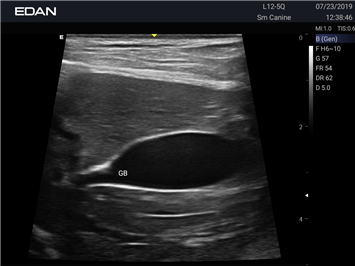

УЗИ-аппарат

EDAN Acclarix AX2 VET

Ветеринарный ультразвук одним нажатием. Система Acclarix AX2 VET разработана с целью обеспечить бескомпромиссную производительность по доступной цене. Наличие уникальных двойных аккумуляторов в легком корпусе массой 4,5 кг из магниевого сплава позволяет системе Acclarix AX2 VET удовлетворять все потребности ветеринарных исследований, сохранив низкую стоимость.

EDAN Acclarix AX2 VET представляет собой специализированную ветеринарную ультразвуковую систему, сочетающую высокую производительность с доступной ценой. Благодаря продуманной конструкции и передовым технологиям, система обеспечивает качественную диагностику животных различных видов.